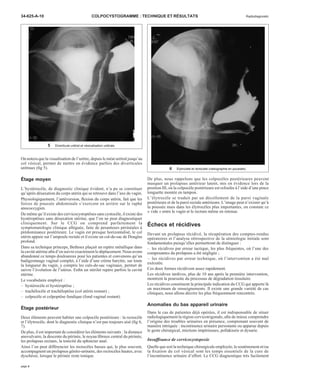

« combiné viscéral » (fig 1). Sous l’effet de la contraction des releveurs,

1 Diagramme normal. Radio-graphies

en retenue et en poussée.